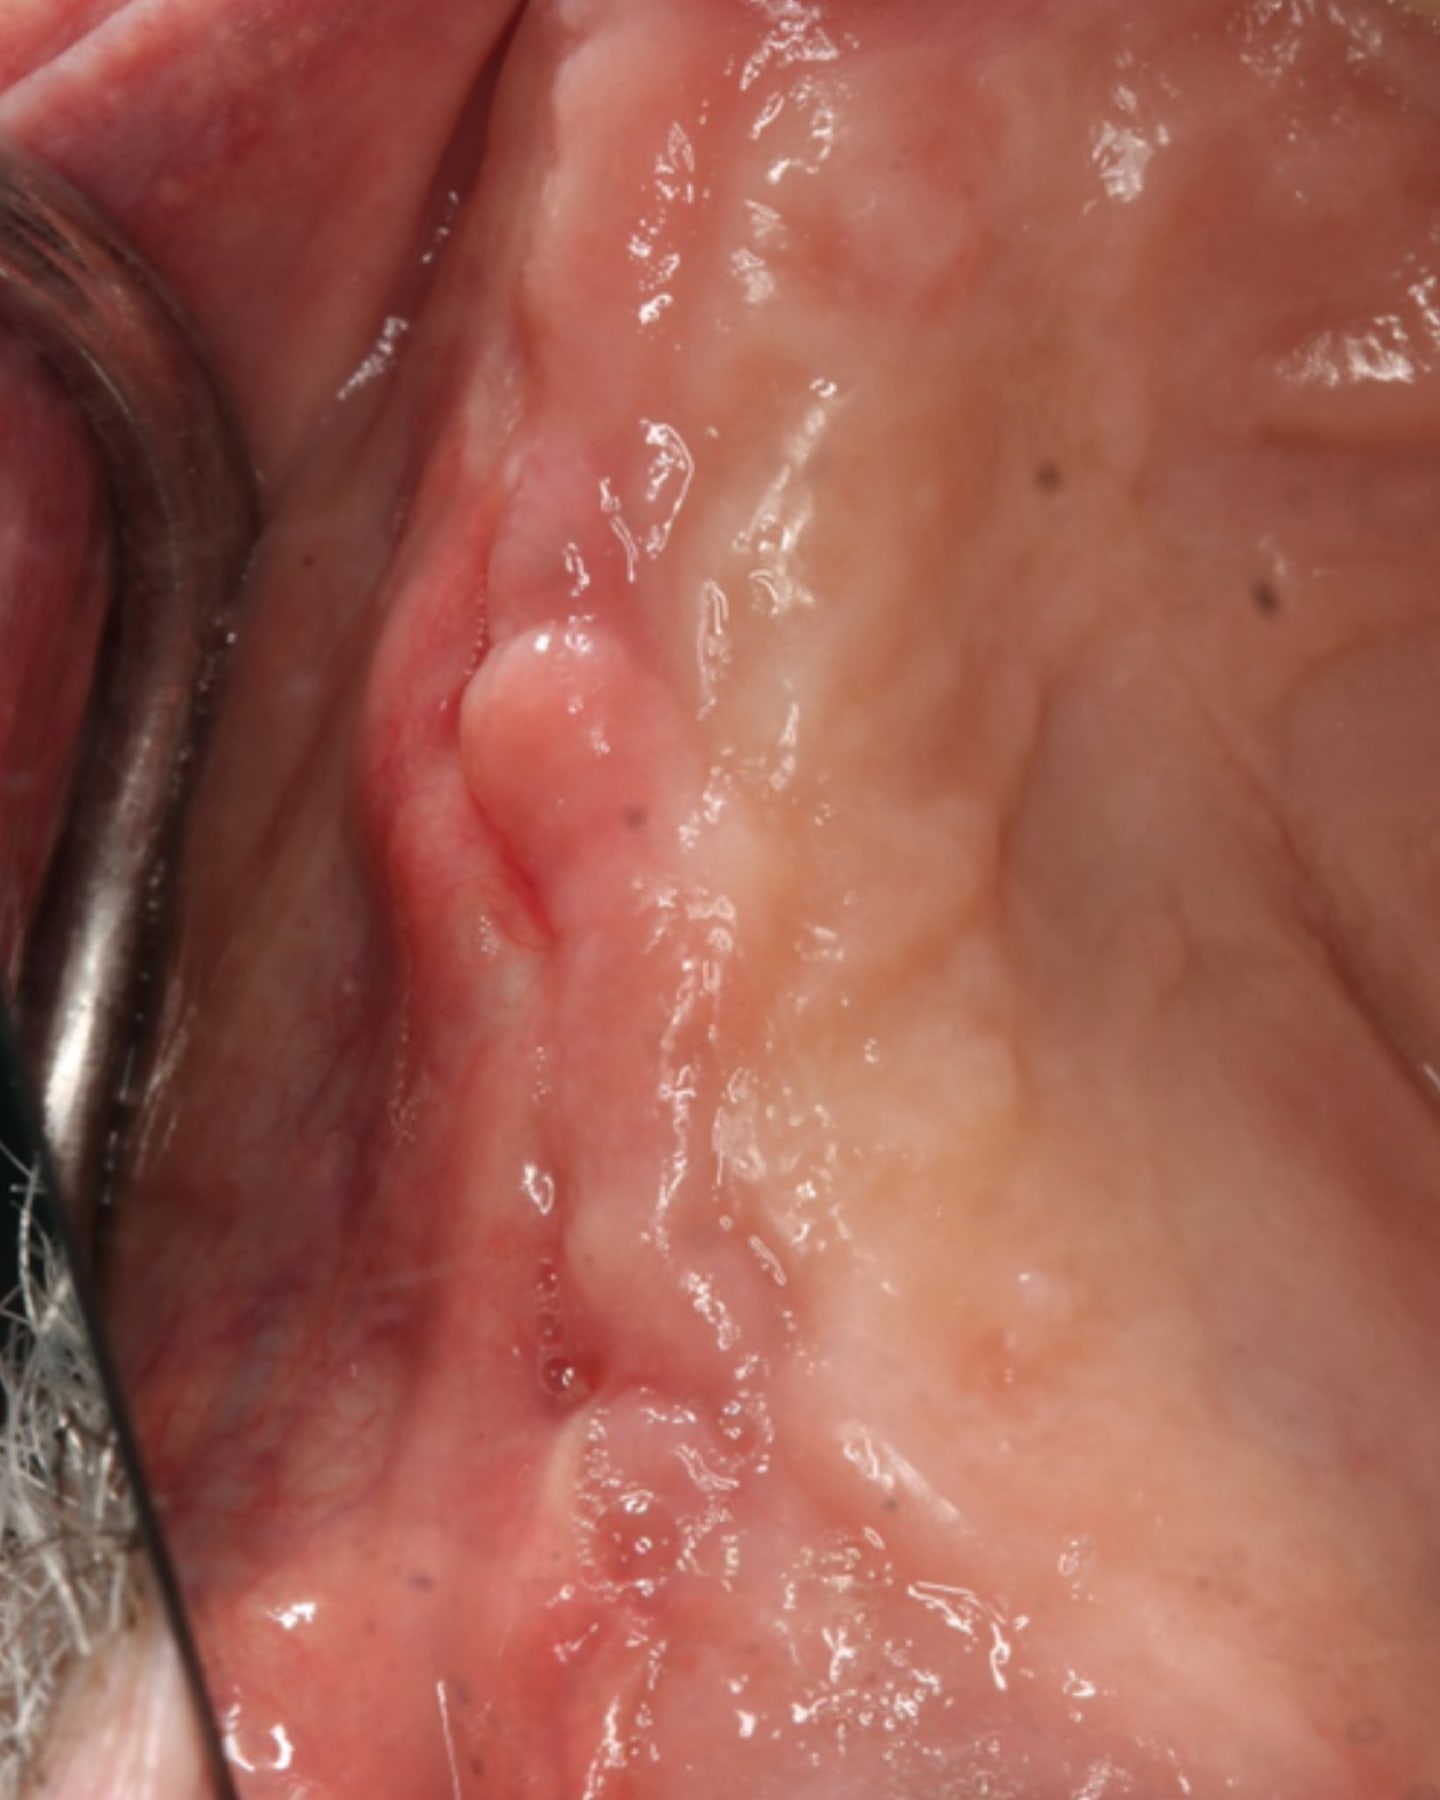

A 76-year-old male patient presented for extraction of the non-restorable teeth in the right maxillary arch. Examination noted a fixed bridge from the right maxillary 1st molar to the right central incisor, and the bridge exhibited Class II mobility. The clinical presentation and findings were discussed with the patient, and a treatment plan involving extraction of teeth, socket grafting, and, following site healing, placement of implants.

The bridge was sectioned and removed (Figure 3). The 1st molar, residual root at the 2nd premolar, canine, and central incisor were atraumatically extracted. The extraction sockets were cleaned and debrided (Figure 4). A block was fabricated from L-PRF derived from the patient’s blood and combined with cortico-cancellous bone (Maxxeus, Kettering, Ohio). The extraction sockets were filled with the graft, and edentulous areas were grafted to restore ideal volume (Figure 5). A BioXclude amnion-chorion barrier membrane (Maxxeus) was placed over the graft material, tucked under the flap margins, and the site was closed with PGA sutures (Figure 6). The patient was provided with a PTech LMHFV device and instructed to use it twice daily for the recommended 5 minutes each session and continue until returning for the post-operative appointment.

At the 6-month post socket grafting appointment the patient presented to initiate implant placement into the grafted ridge. They indicated that since the extraction and socket grafting appointment they had continued to use the PTech LMHFV device twice daily. Soft tissue overlaying the posterior right quadrant demonstrated healthy keratinized non-inflamed tissue (Figure 7). Radiographs were taken that demonstrated dense bone in the socket that were grafted blending well with the surrounding host bone (Figure 8).